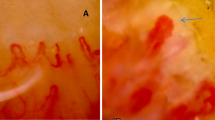

Peripheral blood samples were collected immediately before Iloprost infusion, and at least 1 month after previous administration. Each sample was collected in K2E EDTA tubes and processed within 4 h from bleeding. The first drawn tube was used to determine leukocyte absolute count, in order to enumerate CEC by dual-platform counting procedure. Samples were processed according to the method described by Lanuti et al.20 Briefly, a volume of peripheral blood containing 20 × 106 leukocytes underwent an erythrocyte-lysis step, with 1X Pharm Lyse solution (BD Biosciences) according to manufacturer’s instructions. The washed cellular pellet was resuspended and added to Circulating Endothelial Cells Lyotube (BD Biosciences), containing a lyophilized cocktail of: 7-AAD, CD45 APC-H7; CD34 PE-Cy7; CD146 PE; CD309 AlexaFluor647. 50 µl of Syto16 (Invitrogen, USA) 1:1000 was added as liquid drop in. Samples were then incubated for 30′ at 4 °C, washed (2 ml of Stain Buffer with BSA, BD Biosciences) and re-suspended in FACSFlow (BD Biosciences). 3,1 × 106 events/sample with lympho-monocyte morphology (SSC/FSC dot plot) were acquired by flow cytometry (FACSCanto II, standard configurations) and analyzed using BD FACSDiva v 8. Specific analysis gate strategy was used to enumerate live CECs, defined as negative for 7-AAD and CD45, positive for Syto16, CD146 and bright for CD34. Control tube containing isotype control for CD146 PE was used to define the positivity region for this marker (Fig. 2). CEC counts were always expressed as number of cells/ml of peripheral blood. Instrument performances and data reproducibility were checked according to manufacturer’s instructions, before each evaluation.

Flow cytometry characterization of Circulating Endothelial Cells (CEC). Live nucleated lympho-monocytes were assessed for CD45 and CD34 expression (sky-blue dots in plots A, panel and control). The population defined as positive for CD34 and negative for CD45 expression was gated (blue dots), and evaluated for CD146 positivity. CD146 was gated either versus CD45 (plot B panel) and versus CD34 (plot C panel). Real CD34 bright, CD146 positive events (pink dots) resulted from the intersection of gates displayed in plot A, B and C are CECs. The position of these gates was defined on the basis of matched isotype controls (plot B and C control).